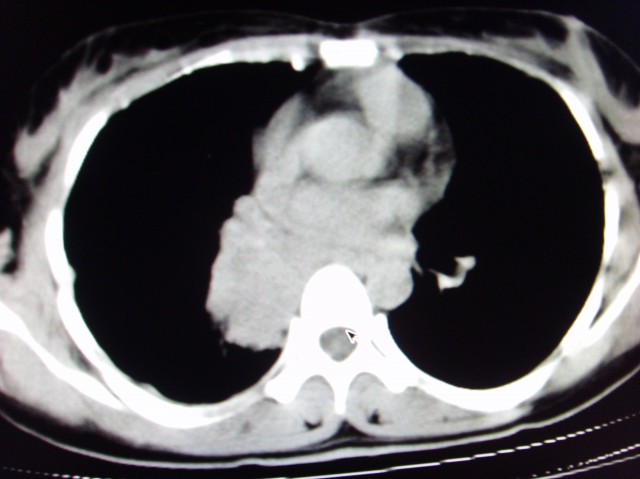

标题: CT7125:中央性肺Ca.

典型 中央型ca伴双肺、淋巴结转移

右下中心型肺癌伴双肺转移、纵隔淋巴结转移,癌性淋巴管炎可能性大

典型--右下中心型肺癌伴双肺转移、纵隔淋巴结转移,癌性淋巴管炎可能性大

典型的中央型ca,肿快和肺门分界不清,肿快边界模糊,呈毛刺状。伴淋巴结转移。